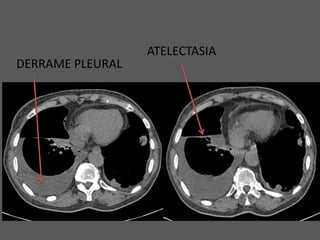

ATELECTASIA

DERRAME PLEURAL